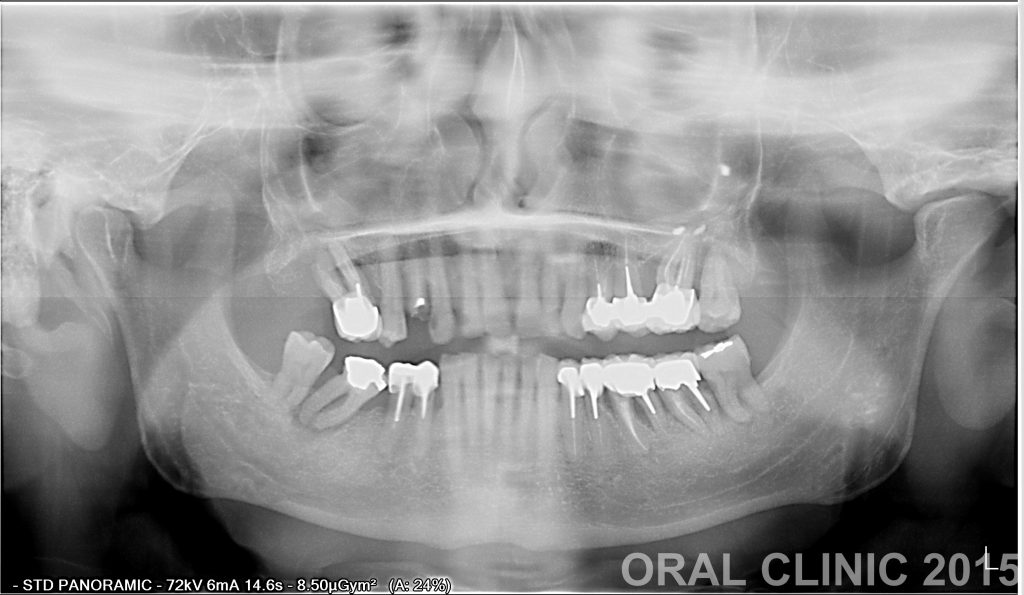

POSE BRIDGE 12 DENTS SUR 8 IMPLANTS ET ELEVATION DU SINUS

BRIDGE 12 DENTS SUR 8 IMPLANTS Elévation de sinus bilatérale , greffe de bloc osseux antérieur, pose de huit implants et bridge de 12 couronnes ceramo metallique.   Chirurgien: Dr. Thierry Hascoet Prosthodonte: Dra. Yanira Peña Laboratoire: Mondental